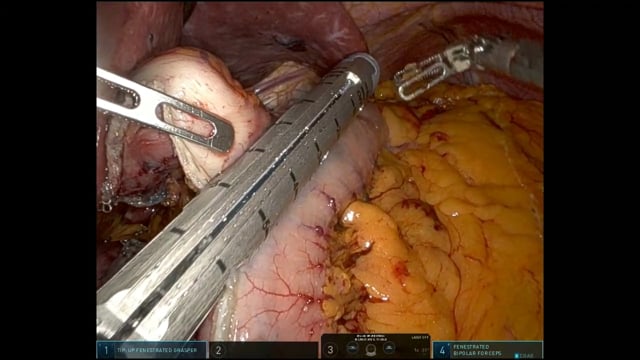

Trattamento chirurgico robotico del cancro dell'esofago secondo la tecnica Ivor Lewis Ramie

Isolamento dell'esofago toracico con tecnica robotica